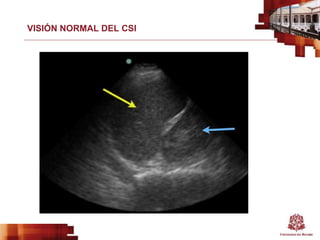

VISIÓN NORMAL DEL CSI

VISIÓN ANORMAL DEL CSI